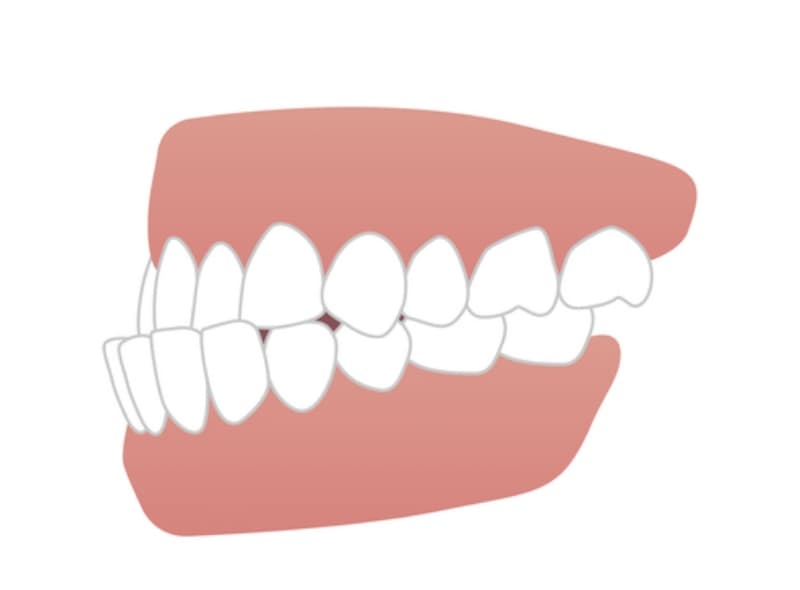

過蓋咬合

上の前歯が下の前歯を大きく覆っている状態を指します。過蓋咬合は、

前歯の異常な摩耗や歯周組織への過剰な負担を引き起こし、顎関節症の原因にもなり得ます。また、笑顔の印象を悪くするため、審美的な問題も生じます。